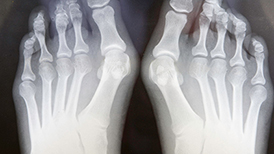

This guide explains what bunion surgery involves, why it is performed, the recovery process and how the right mobility aid can help you stay independent while healing.

Did you know that many of our knee scooter rental customers have recently had Bunion surgery? Read our article regarding bunion surgery and how our StrideOn knee walker can help with your recovery.